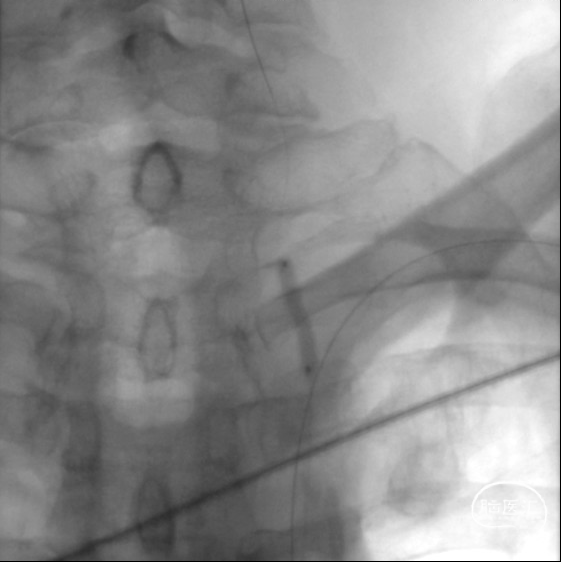

造影见LV闭塞,立即沿0.014*200cm 通桥北斗SS™神经血管导丝置入3mm*16mm 药物球扩支架至LV1。

压力泵逐渐加压球扩支架到8atm, 支架打开良好,造影示残余狭窄0%。

双侧锁骨下动脉造影见椎动脉、基底动脉血流通畅,远端未见栓塞表现。